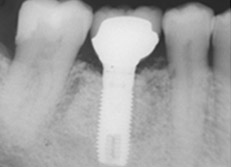

下顎大臼歯部のインプラント

この症例は、保存が困難な第一大臼歯をインプラントで治療した例です。

治療前

アバットメントの装着後

8年後